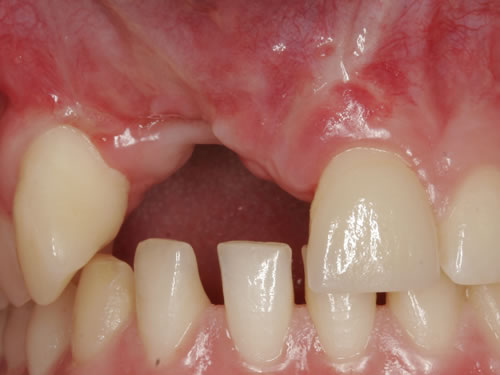

Im Alter von 12 Jahren hatte ein jetzt 20-jähriges Mädchen durch einen Skateboardunfall zwei Schneidezähne im Oberkiefer verloren (Abb. 3.33). Zunächst wurden die Zähne wieder eingesetzt, doch nach 2 Jahren lösten sich die Wurzeln auf und mussten entfernt werden (Abb. 3.34). Damit das Mädchen nicht ohne Zähne herumlaufen musste, wurden beide Frontzähne durch eine kleine Prothese ersetzt (Abb. 3.35). Das Mädchen hat die Prothese ohne zu klagen regelmäßig getragen. Inzwischen sträubt sie sich allerdings gegen diesen herausnehmbaren Zahnersatz, da sie einen Freund gefunden hat und ihr das Tragen der Prothese jetzt unangenehm ist. Die Lücke wurde durch 2 Implantate und Einzelkronen geschlossen (Abb. 3.36).

Abb. 3.33: Ausgangsbefund mit 2 entzündeten und zerstörten Zähnen nach Unfall.